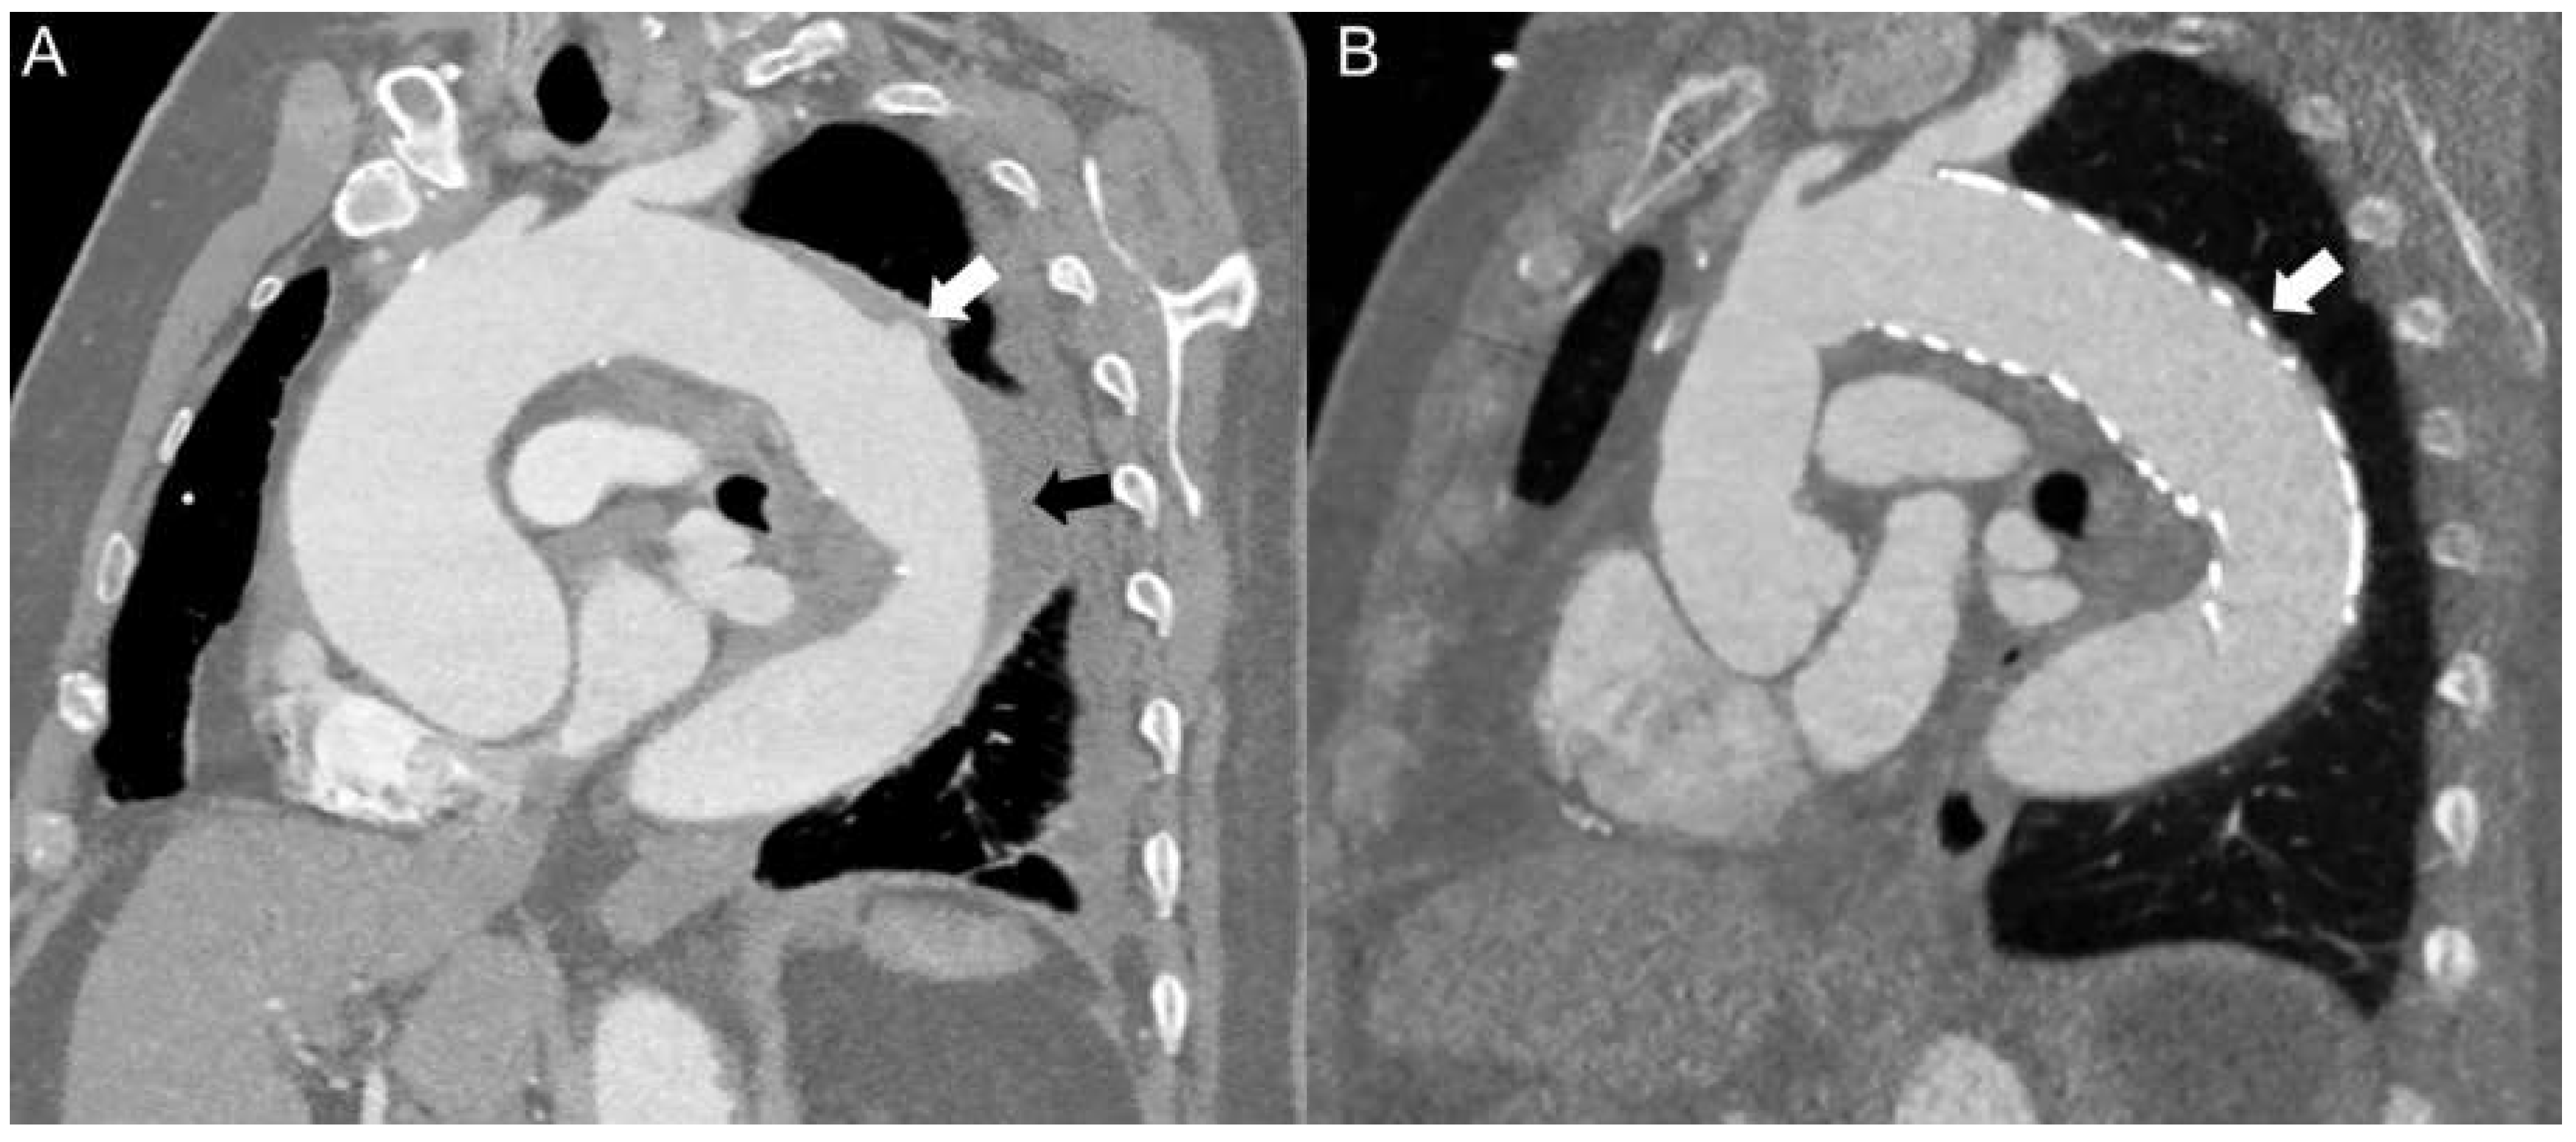

Clinical summary